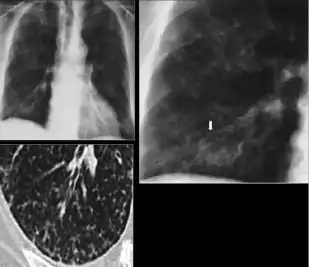

3. Nodule with poorly defined margins - Round density within the lung parenchyma, also called a tuberculoma. Nodules included in this category are those with margins that are indistinct or poorly defined (tree-in-bud sign[3]). The surrounding haziness can be either subtle or readily apparent and suggests coexisting airspace consolidation.

Chest x-ray showing nodule with margins that are indistinct or poorly defined (tree-in-bud sign) in post-primary pulmonary TB.